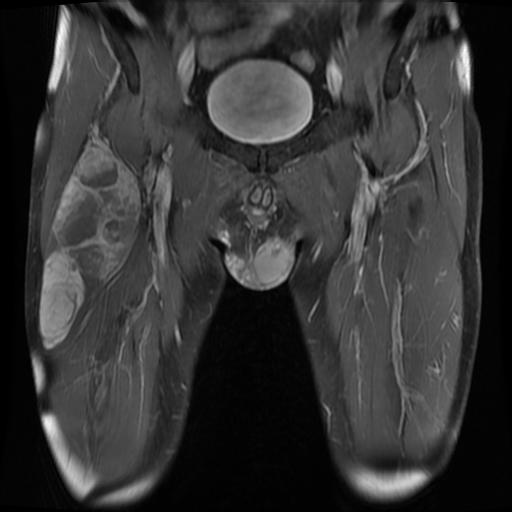

Rhabdomyosarcoma - Pathology - Orthobullets

www.orthobullets.com

www.orthobullets.com

rhabdomyosarcoma orthobullets mri pathology 51a donnell patrick topic

Successful Treatment Of Adult Pleomorphic Rhabdomyosarcoma In The

www.scirp.org

www.scirp.org

rhabdomyosarcoma femur mri pleomorphic posterior treatment thigh examination mass

Rhabdomyosarcoma pleomorphic thigh case examination gross misdiagnosis primary adult young right report figure ol. Rhabdomyosarcoma femur mri pleomorphic posterior treatment thigh examination mass. Newborn rhabdomyosarcoma leg lower